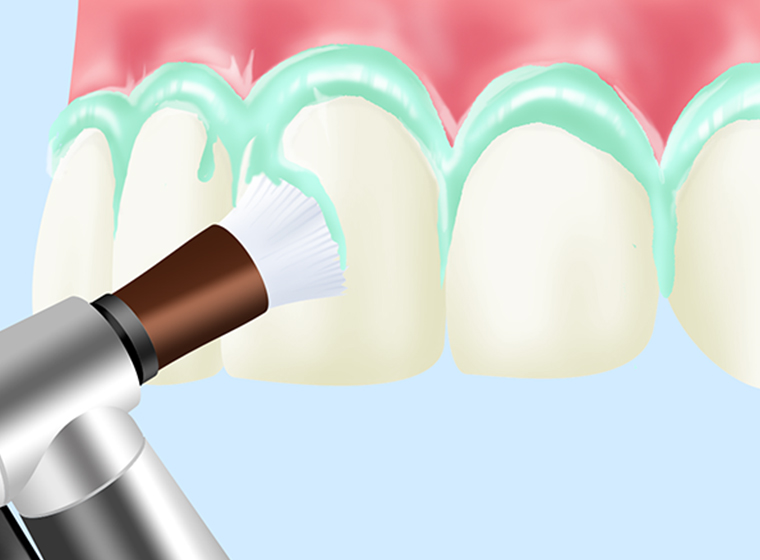

PMTC

PMTCとは(プロフェッショナル・メカニカル・トゥース・クリーニング)の略で、専用の器具を使って歯をクリーニングします。毎日のセルフケアでは落としきれない歯と歯の間や歯周ポケットの汚れをきれいに落とします。口臭予防にもつながり、軽度の色素沈着も除去可能です。